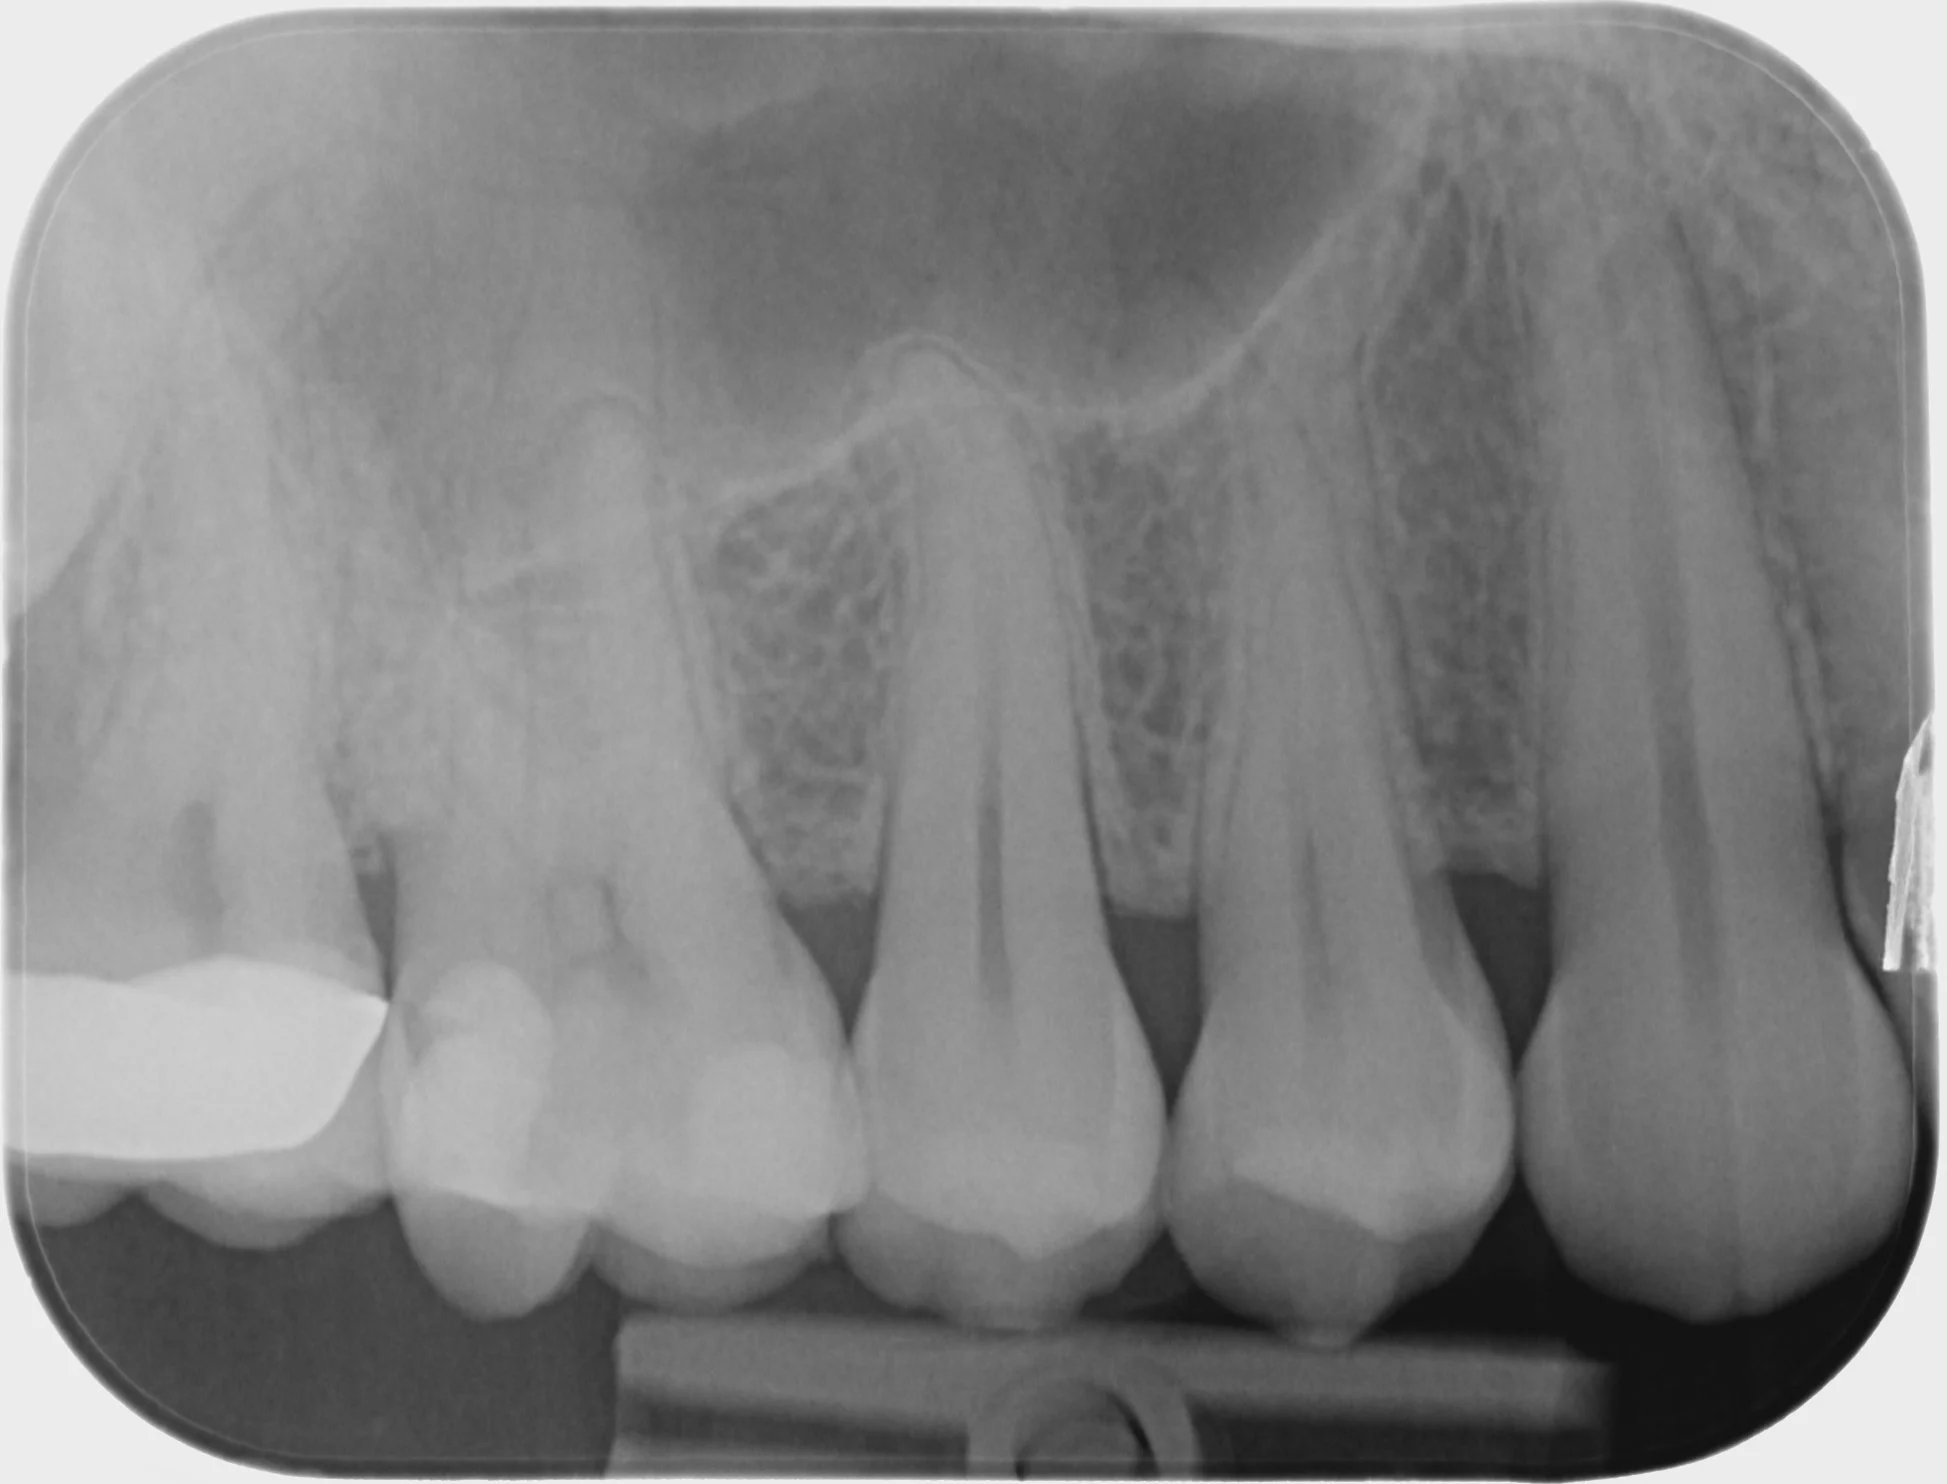

Fixed pros

Dental Implants

Endodontics